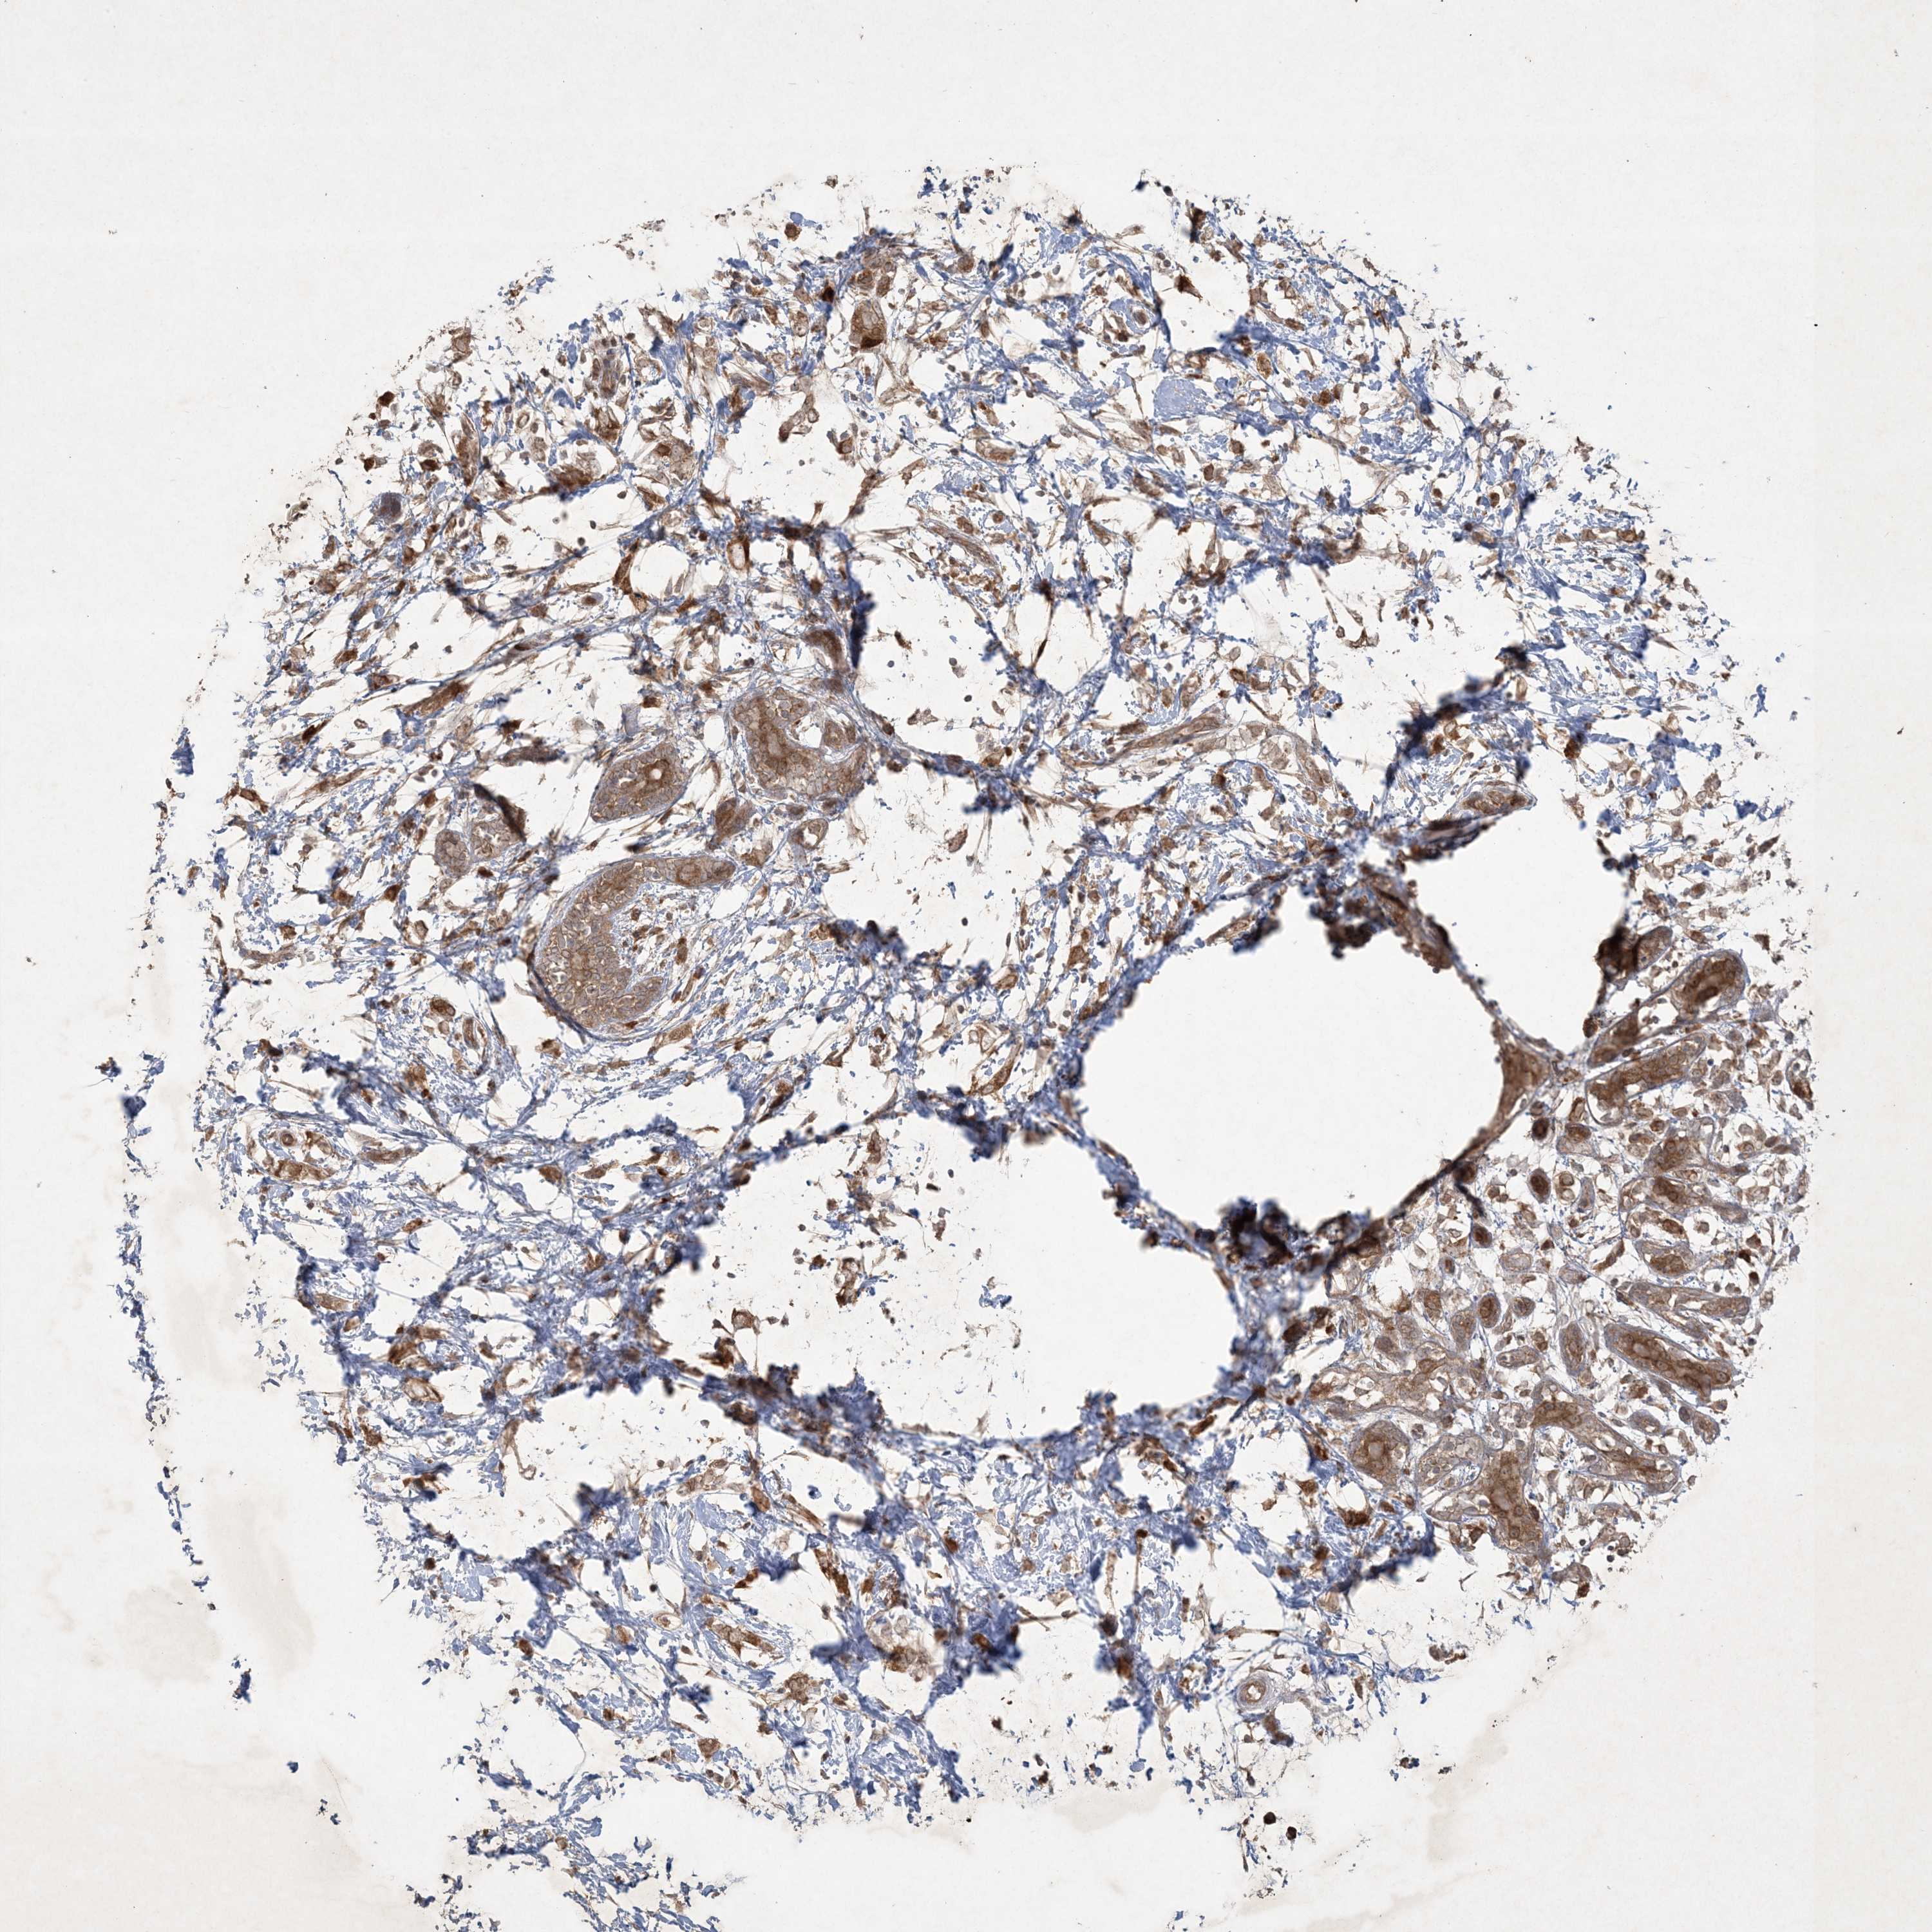

CANCER BREAST CANCER Show tissue menu

Breast cancer

Human cancer